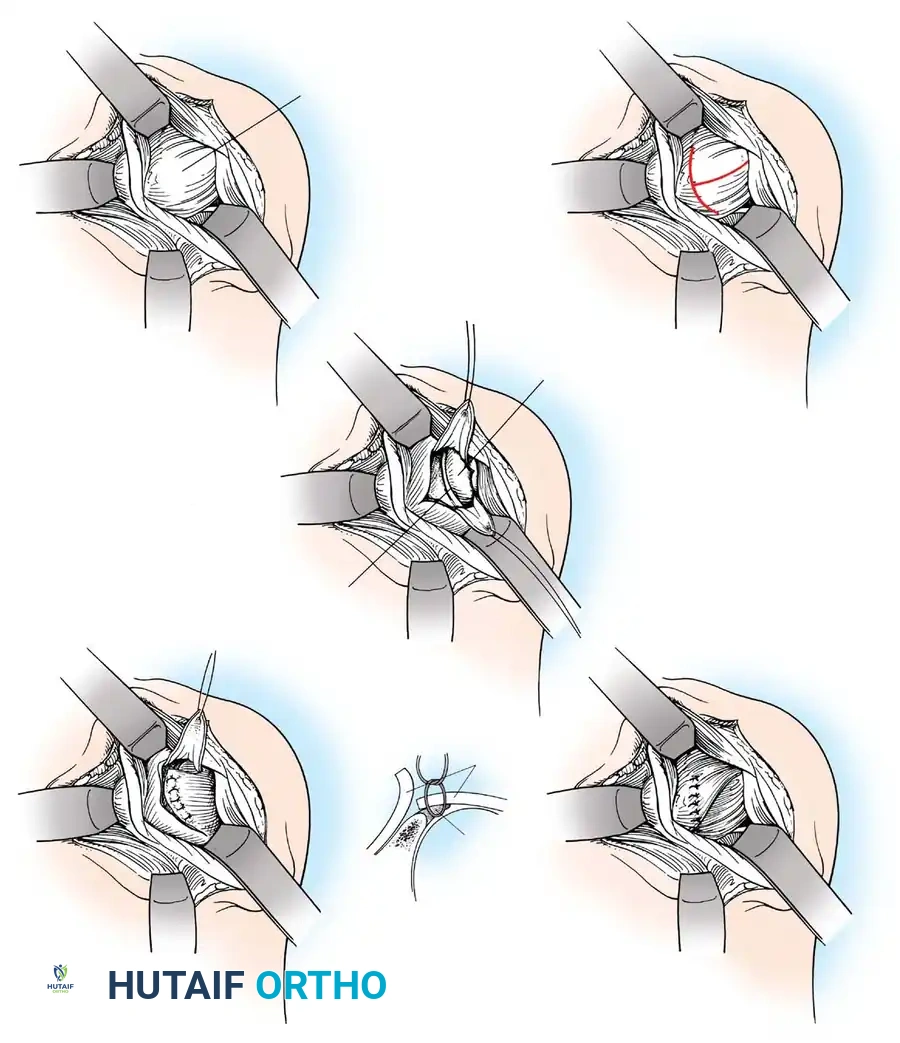

Exposure of the anterior capsule requires navigating the subscapularis muscle. Historically, a vertical tenotomy was performed; however, modern techniques favor a subscapularis split or a peel to preserve the integrity of the muscle belly and its tendinous insertion.

- The Split: A horizontal split is made in the subscapularis at the junction of its middle and inferior thirds, extending from the lesser tuberosity medially.

- Separation: The subscapularis is carefully elevated off the underlying anterior joint capsule. This plane can be scarred in revision cases, requiring meticulous sharp dissection to avoid inadvertent capsulotomy.

Capsulotomy and Joint Inspection

A vertical or T-shaped capsulotomy is performed based on the degree of capsular laxity and the planned shift.

- For a standard Bankart repair with an inferior capsular shift, a vertical incision is made 1 cm medial to the humeral articular margin. A horizontal limb can be added to create superior and inferior capsular flaps.

- Tagging sutures are placed in the capsular flaps for traction.

- A Fukuda retractor is placed within the joint to retract the humeral head laterally and posteriorly, exposing the anterior glenoid rim and labrum.

Glenoid Preparation and Labral Repair

The essential step in restoring stability is the anatomical reduction of the capsulolabral complex to a bleeding bone bed on the anterior glenoid rim.

- Debridement: The anterior glenoid neck is decorticated using a motorized burr, rasp, or osteotome to create a bleeding cancellous bed. This promotes robust biological healing of the repaired labrum.

- Mobilization: The scarred, medially displaced labrum (ALPSA lesion) must be fully mobilized using a periosteal elevator until the subscapularis muscle belly is visible anteriorly. The tissue must float freely to be shifted superiorly and laterally.

- Anchor Placement: Suture anchors (typically 3 to 4) are placed along the articular margin of the anteroinferior glenoid (from the 5:30 to 3:00 positions for a right shoulder). Anchors must be inserted at a 45-degree angle to the articular surface to maximize pullout strength and avoid joint penetration.

Capsular Shift and Closure

To address capsular redundancy, an inferior capsular shift is performed.

- The arm is positioned in 30 to 45 degrees of abduction and 20 degrees of external rotation.

- The inferior capsular flap is advanced superiorly and laterally, tensioning the IGHL complex. The sutures from the anchors are passed through the shifted capsule and tied.

- The superior flap is then brought down over the inferior flap in a "pants-over-vest" fashion to reinforce the anterior wall and close the rotator interval.

- The subscapularis split is loosely approximated with absorbable sutures. The deltopectoral interval is closed over a suction drain (if necessary), followed by routine subcutaneous and skin closure.